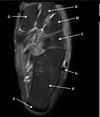

1

Q

What is letter A?

A

SUPRASPINATUS TENDON

How well did you know this?

2

What is letter B?

ACROMION

Not at all

3

4

5

Perfectly